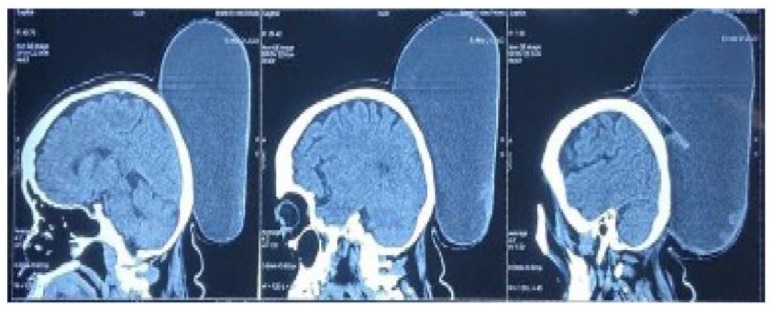

During the inspection, a swelling in the bilateral parieto-occipital region of the scalp was observed. The swelling measured 26x24x12 cm and had a globular shape with a lobulated surface. It had clearly defined edges,was soft, painless, non-tender, cystic, and showed no signs of infection. There was no evidence of expansile or pulsatile pulsations, and no impulse was observed on coughing. The overlying skin had normal color with venous engorgement, but there were no signs of redness or edema. Additionally, there was ulceration on the apex of the swelling. The transillumination test was negative.thin walled, cystic fluid collection of size 26 x 24 x 12 cm seen arising from deep scalp layers of left parieto-occipital region, extending from midline posterior high parietal region up to posterior aspect of occipital bone abutting their outer cortices and with normal underlying bone with no intra-cranial extension of the lesion (Figure 2).

Figure 2 : Preoperative NCCT Head-Saggital cuts.

The patient was diagnosed with a large epidermoid cyst based on the findings. Lipoma and dermoid cyst were also considered as potential differential diagnoses. A preoperative Non-Contrast-CT scan of the skull was done to check for any bony or intracranial involvement. The scan revealed a large multiloculated, thin-walled, cystic fluid collection measuring 26 x 24 x 12 cm. The cyst was found in the deep scalp layers of the left parieto-occipital region and extended from the midline posterior high parietal region up to the posterior aspect of the occipital bone, abutting their outer cortices, with normal underlying bone with no intracranial extension of the lesion.On preoperative Magnetic Resonance Imaging (MRI), a large cystic lesion was detected in the scalp region between the parietal and occipital lobes. The lesion was well-defined, had multiple compartments, and measured around 26 cm × 24 cm × 12 cm. The cystic lesion did not affect the skull or brain. On T2-weighted images, the lesion appeared homogeneous with a high-intensity signal (Figure 3).